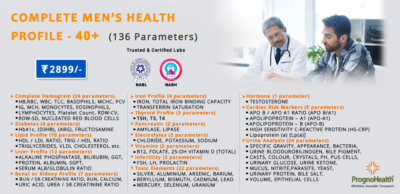

Top rated products

Full Body Health Checkup I

Rated 5.00 out of 5

Full Body Health Checkup I

Rated 5.00 out of 5₹3,000.00Original price was: ₹3,000.00.₹1,770.00Current price is: ₹1,770.00. -

MFG IND PACK III

MFG IND PACK III

₹3,900.00Original price was: ₹3,900.00.₹2,145.00Current price is: ₹2,145.00. -

Dengue NS1 Antigen Test

₹900.00

Dengue NS1 Antigen Test

₹900.00

-

Lipoprotein (A) Blood Test – Lp(a)

₹750.00

Lipoprotein (A) Blood Test – Lp(a)

₹750.00

-

Healthy Life Advance Male

Healthy Life Advance Male

₹15,000.00Original price was: ₹15,000.00.₹8,250.00Current price is: ₹8,250.00.